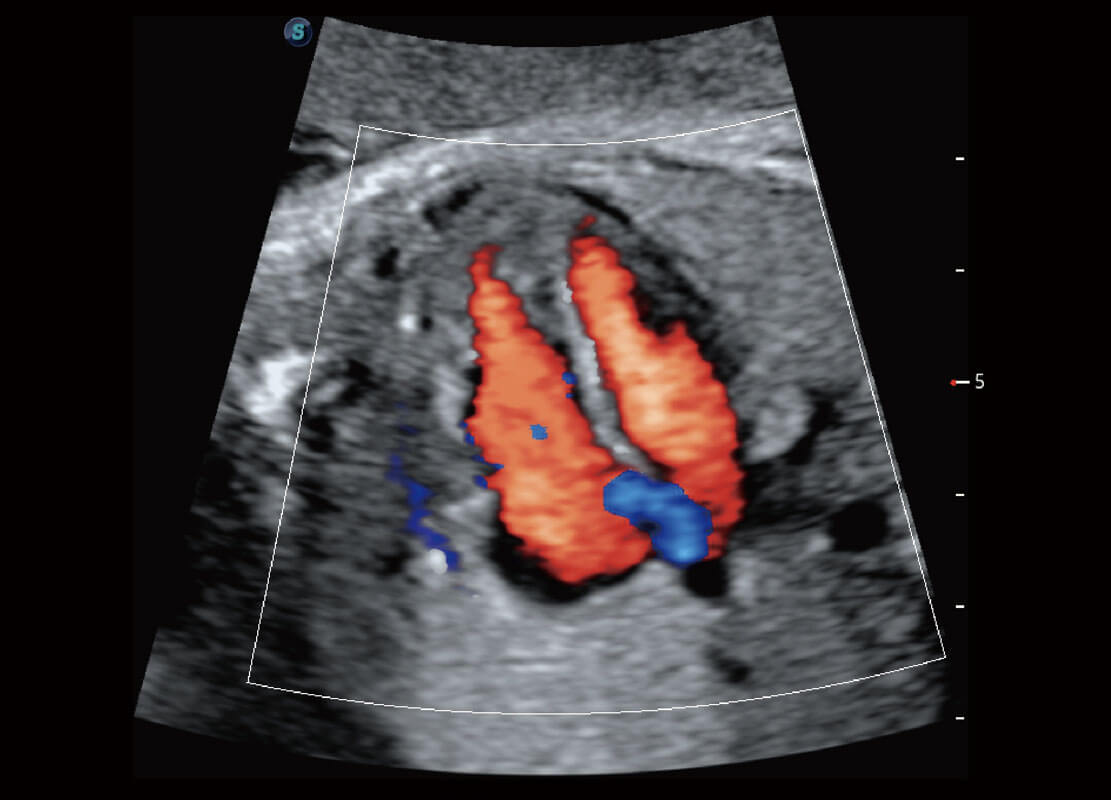

早孕筛查

P60在胎儿早孕期超声筛查中为您带来优异的图像质量。

• 早孕-胎心

• 高分辨率容积成像-早孕胎儿

• 胎儿体循环

• 光影成像-孕囊